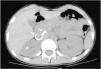

A girl aged 13 years presented with asthenia, decreased appetite, dizziness and abdominal pain of 2 months’ duration. The chief finding of the physical examination were hypertension (HTN) with a blood pressure of 200/135mmHg. The Doppler ultrasound showed an atrophied right kidney with aneurysms in the right renal artery, confirmed by CT angiography (Fig. 1) and arteriography. There was end-organ damage: acute renal failure (peak creatinine, 1.45mg/dL), retinopathy, cardiomyopathy and transient ischaemic attacks in the white matter. The presence of aneurysms in other locations was ruled out with whole-body magnetic resonance angiography.